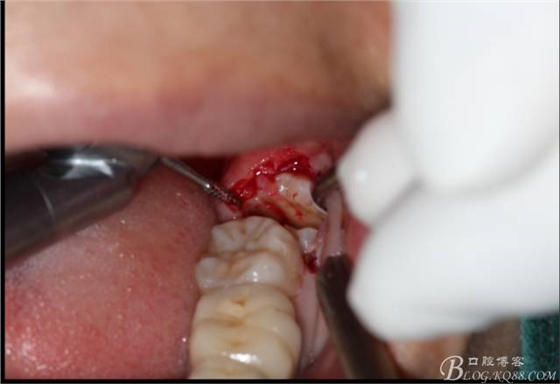

角度鍋輪機(jī)結(jié)合冷鹽水冷卻分冠

640 (11).jpg

分冠完成

640 (12).jpg

取出阻力部分冠

640 (13).jpg

在取出阻力冠后,嘗試性看能取出全部的牙體不,就是取不出也能整體撬動(dòng)牙根。